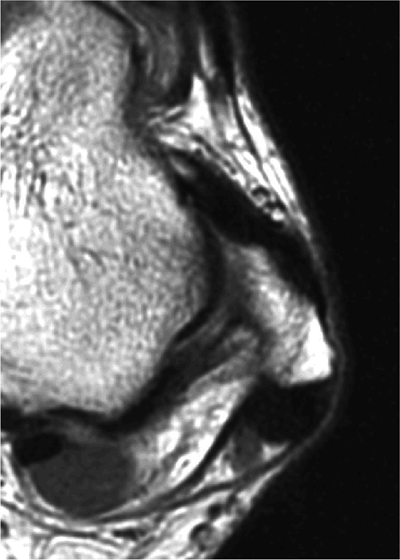

The ATFL is found on sagittal images one slice central to the lateral-most sagittal slice that includes the lateral malleolus. The origin of the ATFL is seen at the anterior inferior tip of the lateral malleolus. The anteromedial course of the ATFL can be followed on the next two images moving centrally, to where it inserts on the talus.

-

The posterior talofibular ligament (PTFL) is located in a similar fashion. The origin of the PTFL is at the inferior tip of the lateral malleolus, and the tendon can be followed medially to its insertion on the mid-posterior aspect of the talus. The PTFL is seen in cross-section on sagittal images and has a cord-like appearance. Posterior to the talus, this cord-like appearance should not be mistaken for a loose body in the posterior joint.